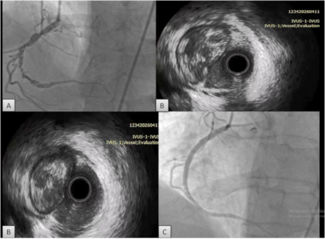

Coronary and graft angiography was performed via left transradial approach. Native coronary angiography revealed left coronary dominance with significant obstruction of the left main coronary artery by a single discrete lesion. The LAD and circumflex arteries were patent but diseased, with the occluded first obtuse marginal branch being supplied by a patent saphenous vein graft. Notably, competitive flow was present in the mid-LAD due to filling from both the proximal native vessel and LIMA graft (Figure 1, Video 1).

Coronary and graft angiography was performed via left transradial approach. Native coronary angiography revealed left coronary dominance with significant obstruction of the left main coronary artery by a single discrete lesion. The LAD and circumflex arteries were patent but diseased, with the occluded first obtuse marginal branch being supplied by a patent saphenous vein graft. Notably, competitive flow was present in the mid-LAD due to filling from both the proximal native vessel and LIMA graft (Figure 1, Video 1).

Based upon competitive flow noted during native vessel angiography, internal mammary graft patency was expected. Surprisingly, the LIMA was found to be proximally occluded (Figure 2). To reconcile the apparent discrepancy, exploration was performed for alternate sources of LAD filling. It was found that the LIMA downstream of the occluded origin filled via a single branch arising directly from the ipsilateral thyrocervical trunk (Figure 3, Video 2). The etiology of the proximal LIMA occlusion remains uncertain, but conceivably could have been related to vessel injury during coronary artery surgery. Regardless, an initial conservative strategy was felt appropriate, with the possibility of percutaneous intervention (native vessel or graft), or repeat CABG in the future, if required.

Based upon competitive flow noted during native vessel angiography, internal mammary graft patency was expected. Surprisingly, the LIMA was found to be proximally occluded (Figure 2). To reconcile the apparent discrepancy, exploration was performed for alternate sources of LAD filling. It was found that the LIMA downstream of the occluded origin filled via a single branch arising directly from the ipsilateral thyrocervical trunk (Figure 3, Video 2). The etiology of the proximal LIMA occlusion remains uncertain, but conceivably could have been related to vessel injury during coronary artery surgery. Regardless, an initial conservative strategy was felt appropriate, with the possibility of percutaneous intervention (native vessel or graft), or repeat CABG in the future, if required.